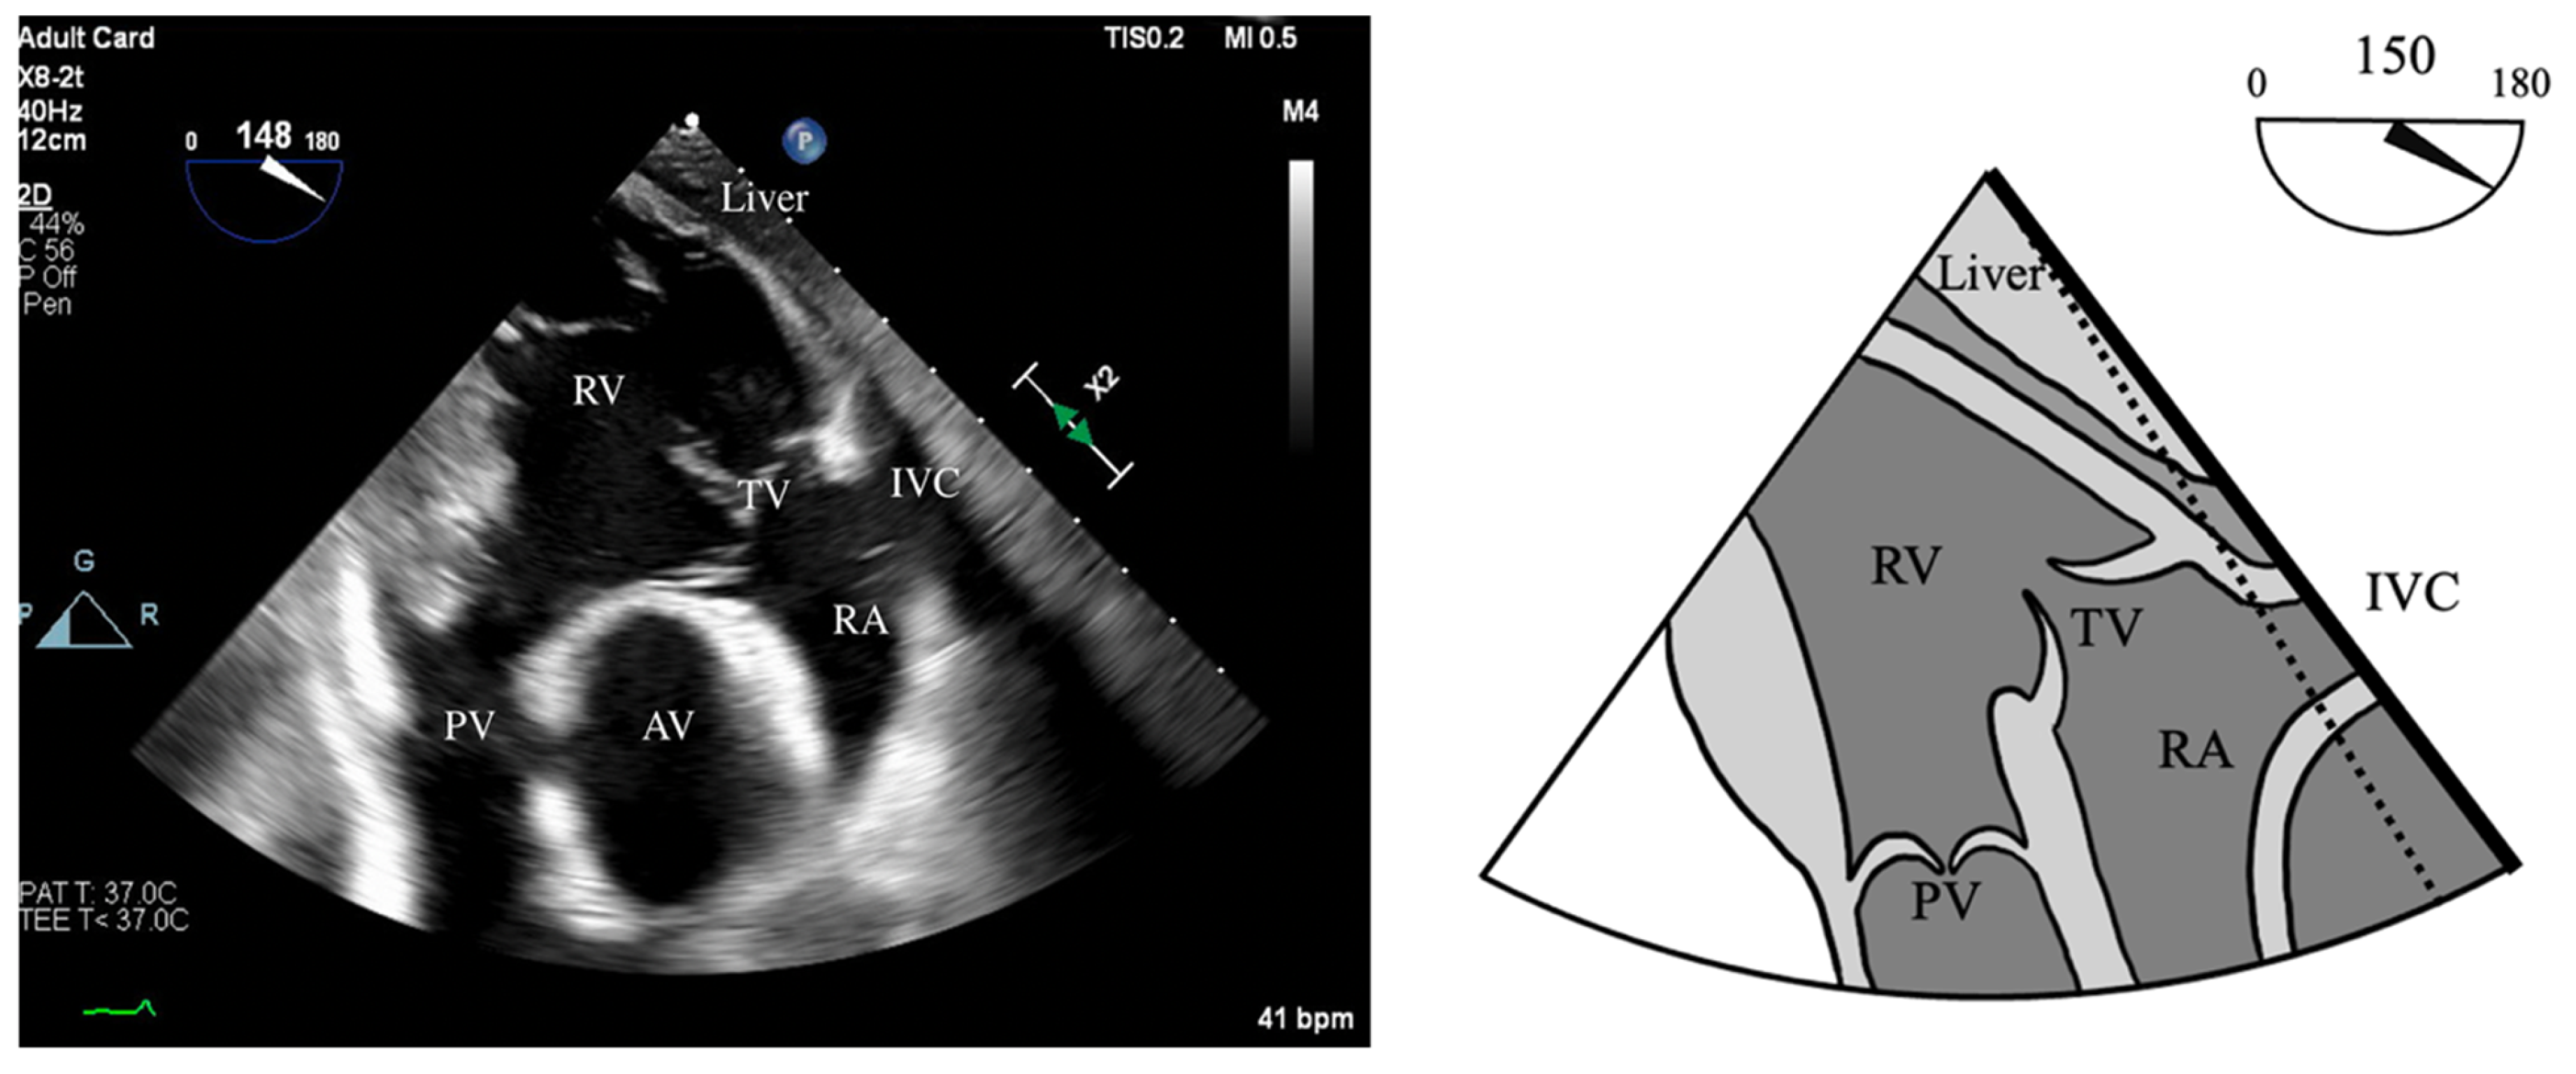

- Vena Contracta Width (VCW): Typically not used for multiple jets. Cutoffs for various grades of PR have not been validated, but most use AI cutoffs (Figure 1).

- VCW/PV ratio has been used with a value of >0.5 consistent with severe PR.

- PWD flow reversal in branched PA: Affected by PA compliance, so brief flow reversals are normal.

- CWD: Through the mPA, watch for envelope density. Dense is consistent with moderate to severe PR, faint is more likely to be mild.

- PR Index: The ratio of PR duration and total diastolic time (regurgitation time/diastole); <0.77 is consistent with severe PR (Figure 2).

- PR Jet Width/RVOT Width: With >65% consistent with severe PR (Figure 3).